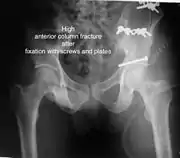

Anterior columnThis fracture is uncommon, typically occurring when the injuring force is applied from the side, against the greater trochanter of the femur bone, as in a fall on the side or being hit on the side. Depending on the location, the fractures are described as very low, low, intermediate and high anterior column fracture. Anterior column + posterior hemi transverseIn this variety of fractures, the posterior or ilio ischial column is broken as a transverse fracture, while the anterior or ilio pubic column is broken into multiple pieces. Part of the weight-bearing dome in this variety of fractures is still attached to that part of the iliac wing, which forms part of the iliac joint. This type of injury has to be differentiated from both column fractures, where the weight-bearing dome is a floating piece not attached directly to the bone-forming sacroiliac joint.

The final management depends on the size of the fragment(s), stability and congruence of the joint. In some cases traction for six to eight weeks may be the only treatment required; however, surgical fixation using screw(s) and plate(s) may be required if the injury is more complex. The latter treatment will be called for if bone fragments do not fall into place, or if they are found in the joint, or if the joint itself is unstable.